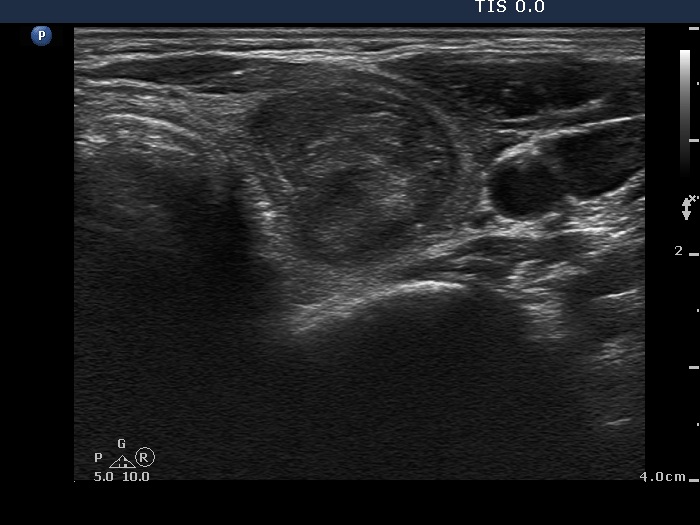

Ethanol sclerotherapy: other examples - Case 3: treatment of a gelatinous thyroid cyst

Six weeks after the therapy (ultrasonographic picture 1)

Right lobe, horizontal scan. The lesion presented a dramatic shrinkage.